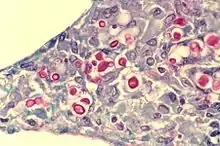

Cryptococcus neoformans (red after staining) in human lung

1. A taxonomic species within the family Tremellaceae – a fungus species that causes cryptococcosis, often fatal in humans.